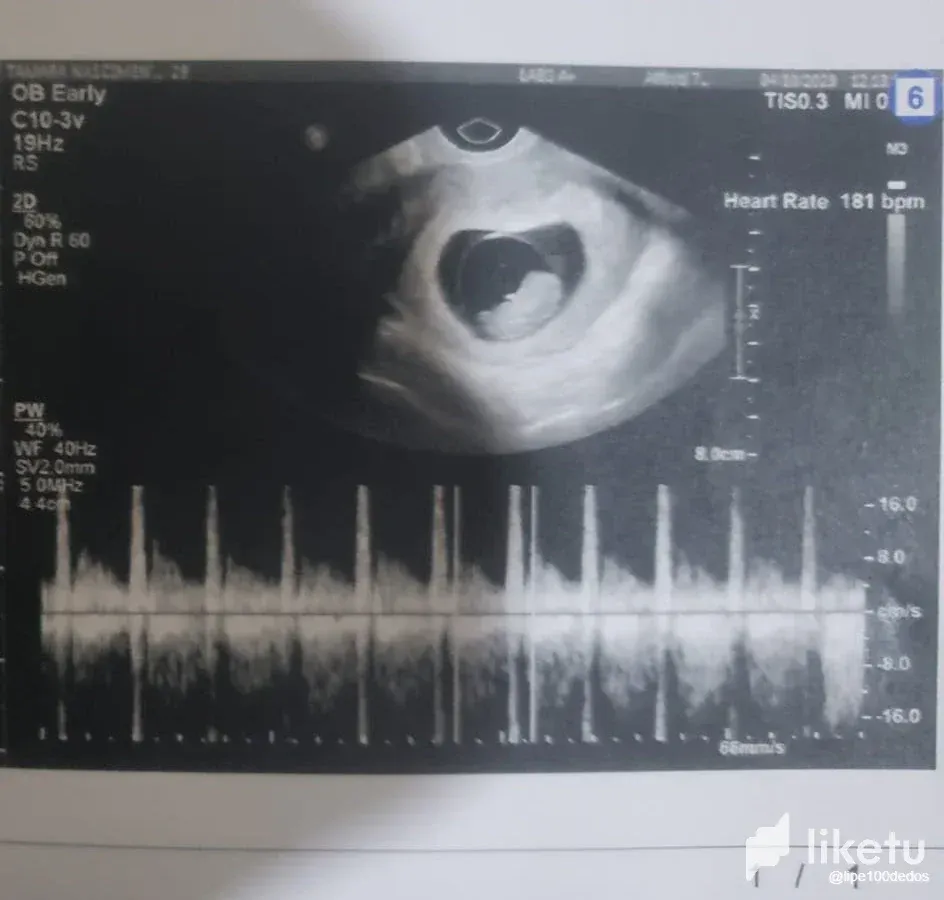

At first there was a mixture of happiness and worry. Due to private issues, I imagined that the pregnancy could be risky, mainly because Tamara had been feeling VERY unwell for a week, and it wasn't the normal unwell feeling of a pregnancy. At the time we decided not to talk about it publicly until we knew how the baby's health was and how the pregnancy was going. But that week we had our first ultrasound after several tests and the news came back that everything was fine! Everything was as expected. Tamara still feels sick, but she's been feeling sick for two weeks, just like in a normal pregnancy. We're still very early in the pregnancy, as you can see from the scans, we're in our 9th week and heading towards our 10th. But just knowing that everything is fine health-wise is already a relief and gives room for happiness.